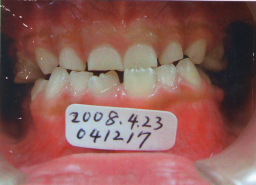

2008年04月23日(6才3ヶ月) 41番(右下切歯)がはえてきました。 反対咬合 |